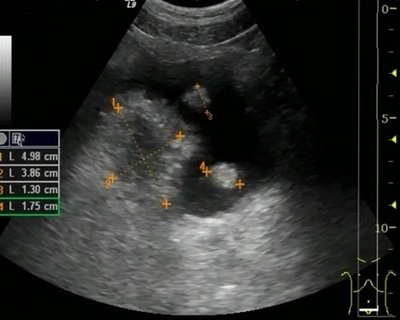

Диагноз: Рак мочевого пузыря T2bNoMo. Кисты правой почки.

Очередной эпизод макрогематурии отметил в начале декабря текущего года. Консультирован в клинике урологии УКБ№2 Первого МГМУ им. И.М.Сеченова, при обследовании (УЗИ, МРТ и МСКТ) диагностировано до 20 объемных образований мочевого пузыря. Госпитализирован в плановом порядке для обследования и лечения.